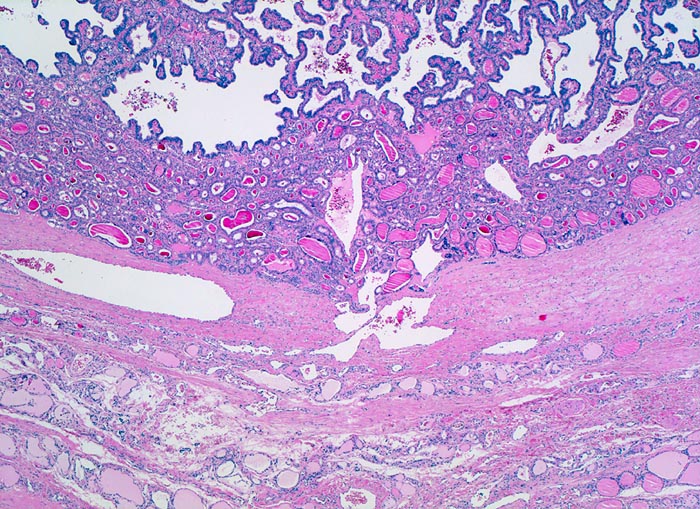

• Scharf begrenzter Tumor mit schmaler Kapsel.

• Links im Bild sind Reste von nicht neoplastischem Schilddrüsenparenchym sichtbar.

• Der Tumor besteht aus Papillen mit einem fibrovaskulären Stromastiel und neoplastischen Follikeln.

• Dicht gelagerte, einander überlappende Tumorzellen mit der typischen Zytomorphologie des papillären Karzinoms:

• Vergrösserte Zellkerne (im Vergleich zu den Zellkernen der nicht neoplastischen Follikelepithelien)

• Zellkerne mit zentraler Aufhellung des Chromatins (Milchglaskerne).

• Kernkerben (Grooves).

• Eindellungen der Kernmembran.

• Kleiner Nukleolus.